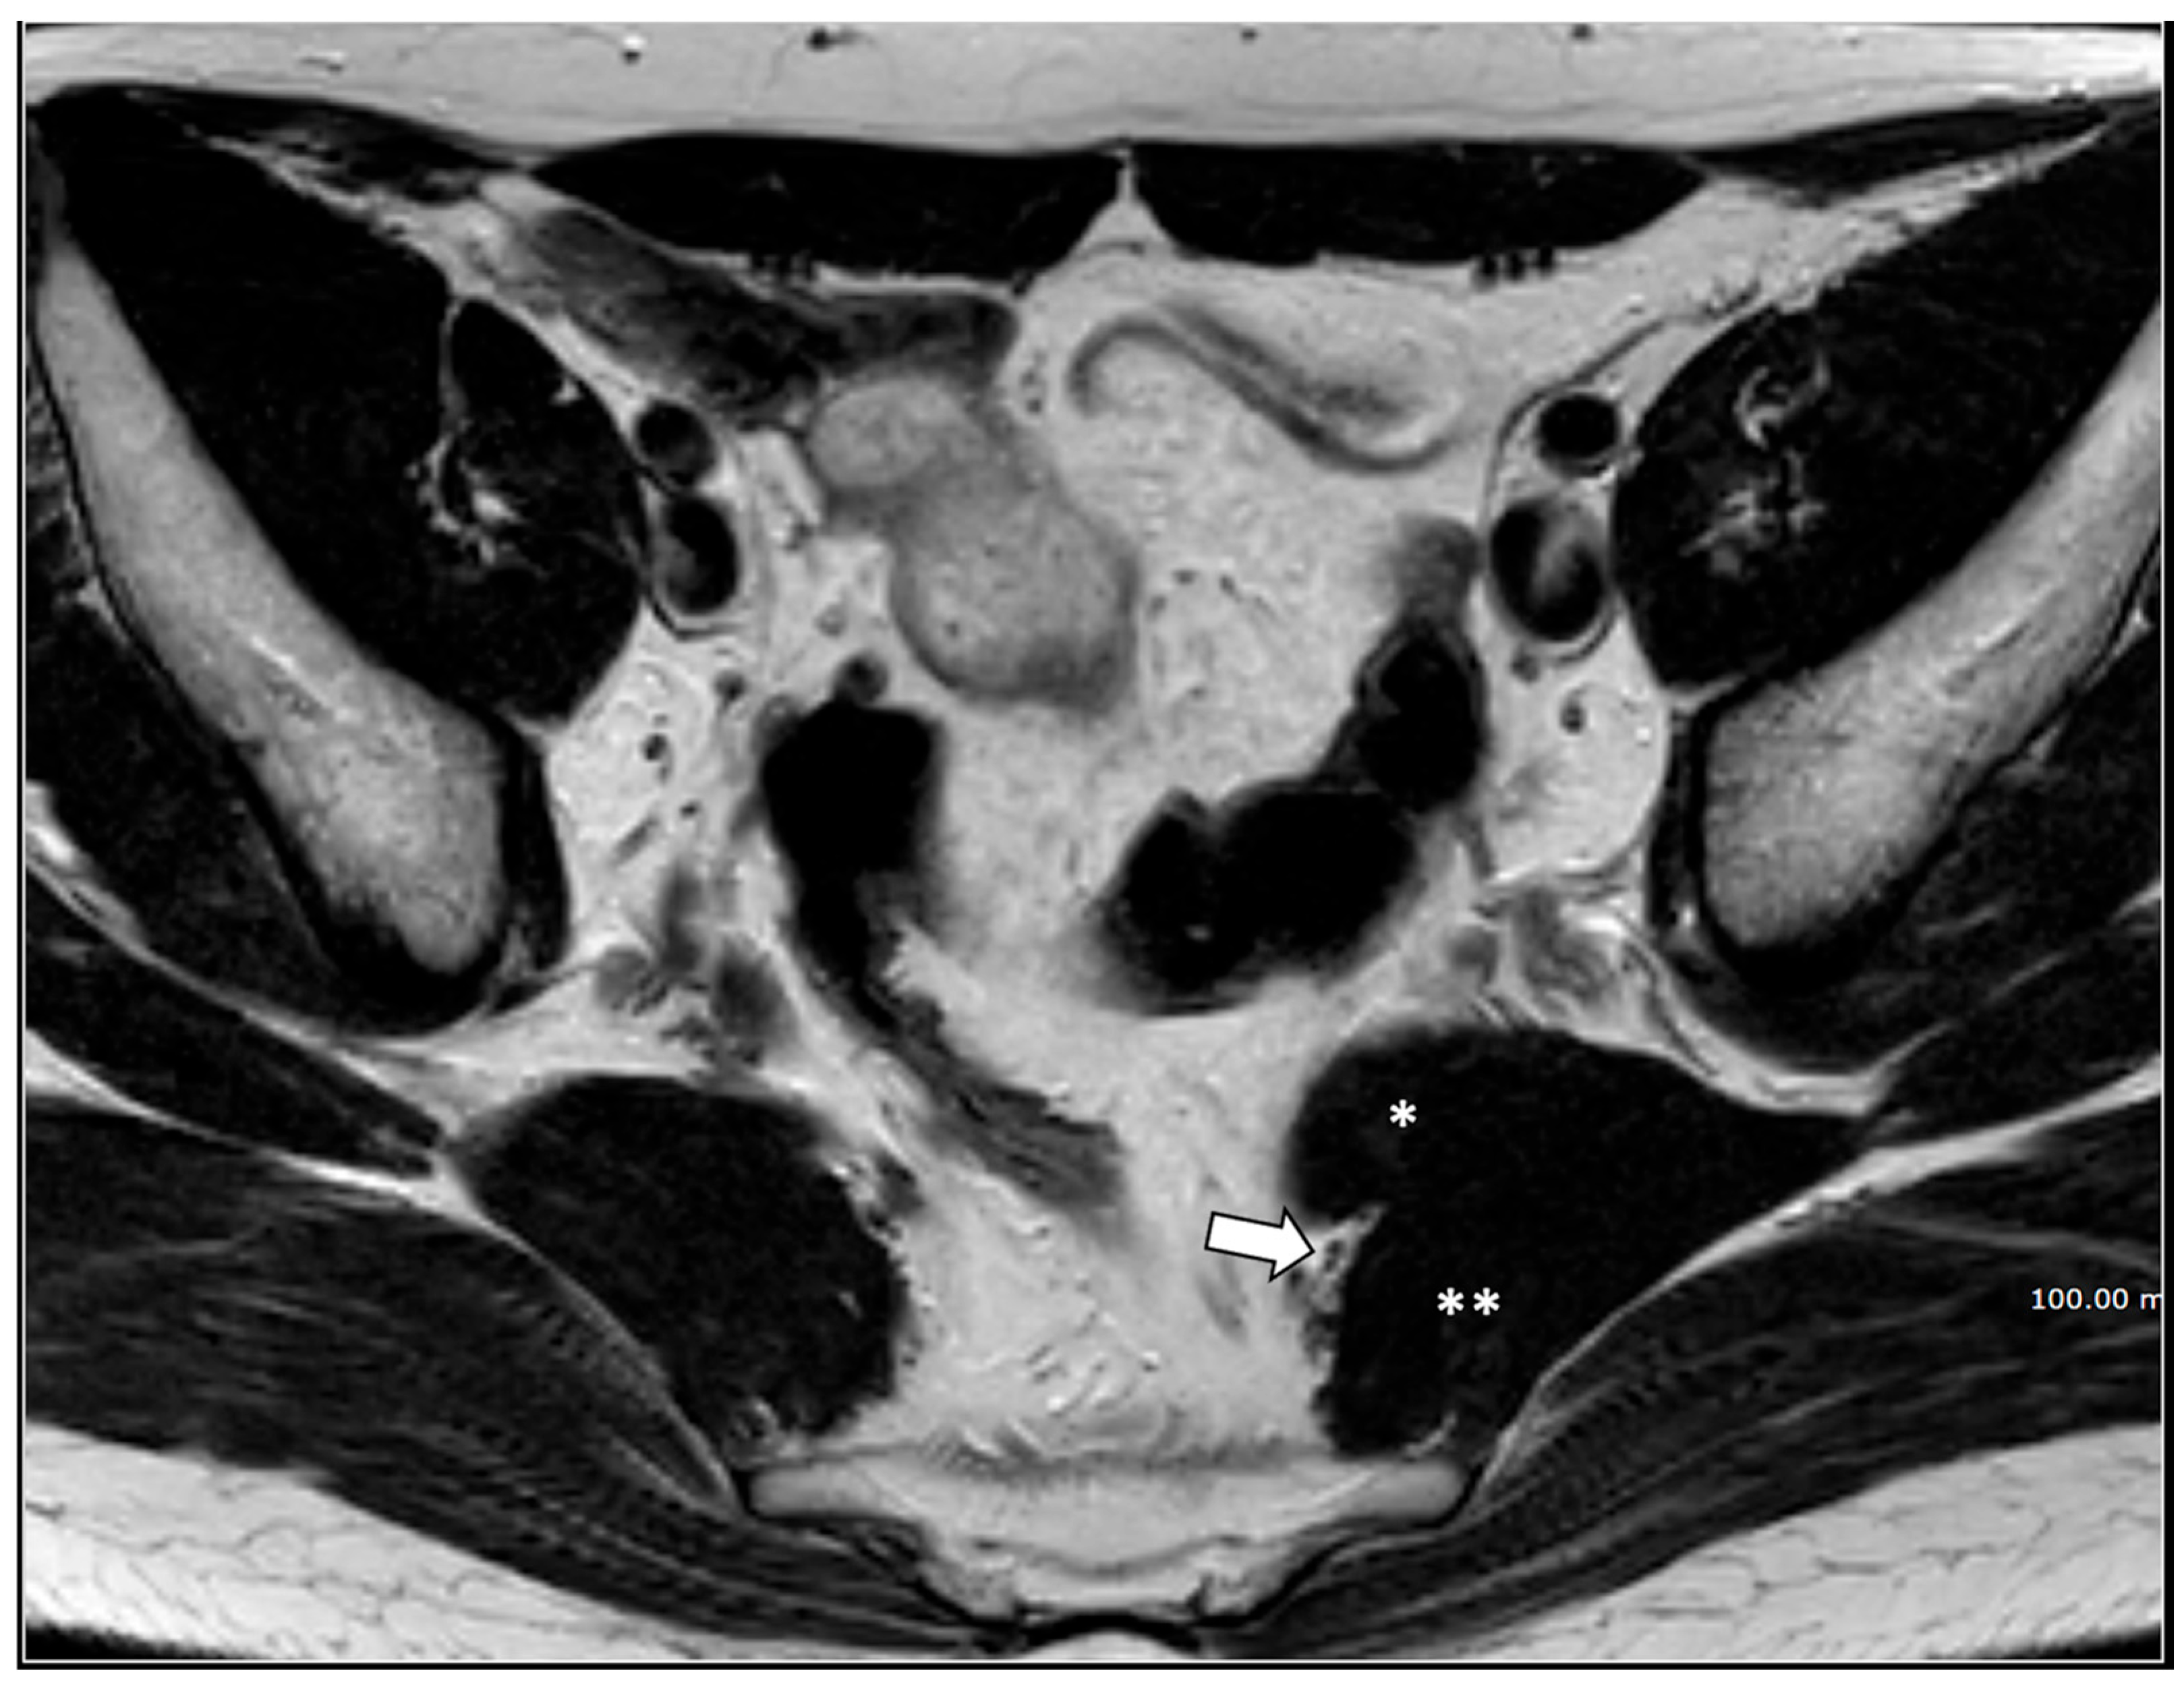

- Giant cyst of the prostatic utricle (1 patient);

- (7)